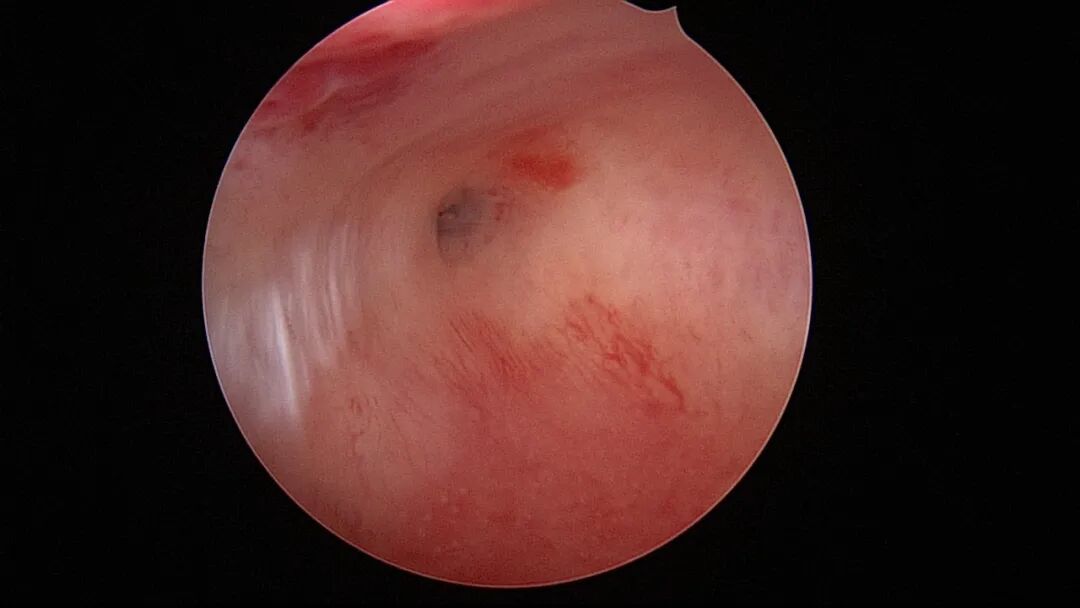

第四次宫腔镜:2021年10月宫腔镜二探取球囊,宫腔形态正常,右侧输卵管开口可见,左侧宫角见瘢痕,左侧输卵管开口隐约可见。